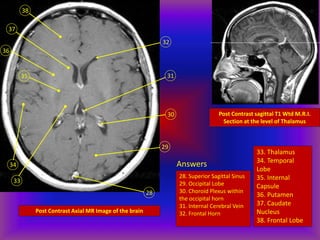

Post Contrast Axial MR Image of the brain

28

29

30

31

32

38

33

34

36

35

37

Post Contrast sagittal T1 Wtd M.R.I.

Section at the level of Thalamus

Answers

28. Superior Sagittal Sinus

29. Occipital Lobe

30. Choroid Plexus within

the occipital horn

31. Internal Cerebral Vein

32. Frontal Horn

33. Thalamus

34. Temporal

Lobe

35. Internal

Capsule

36. Putamen

37. Caudate

Nucleus

38. Frontal Lobe